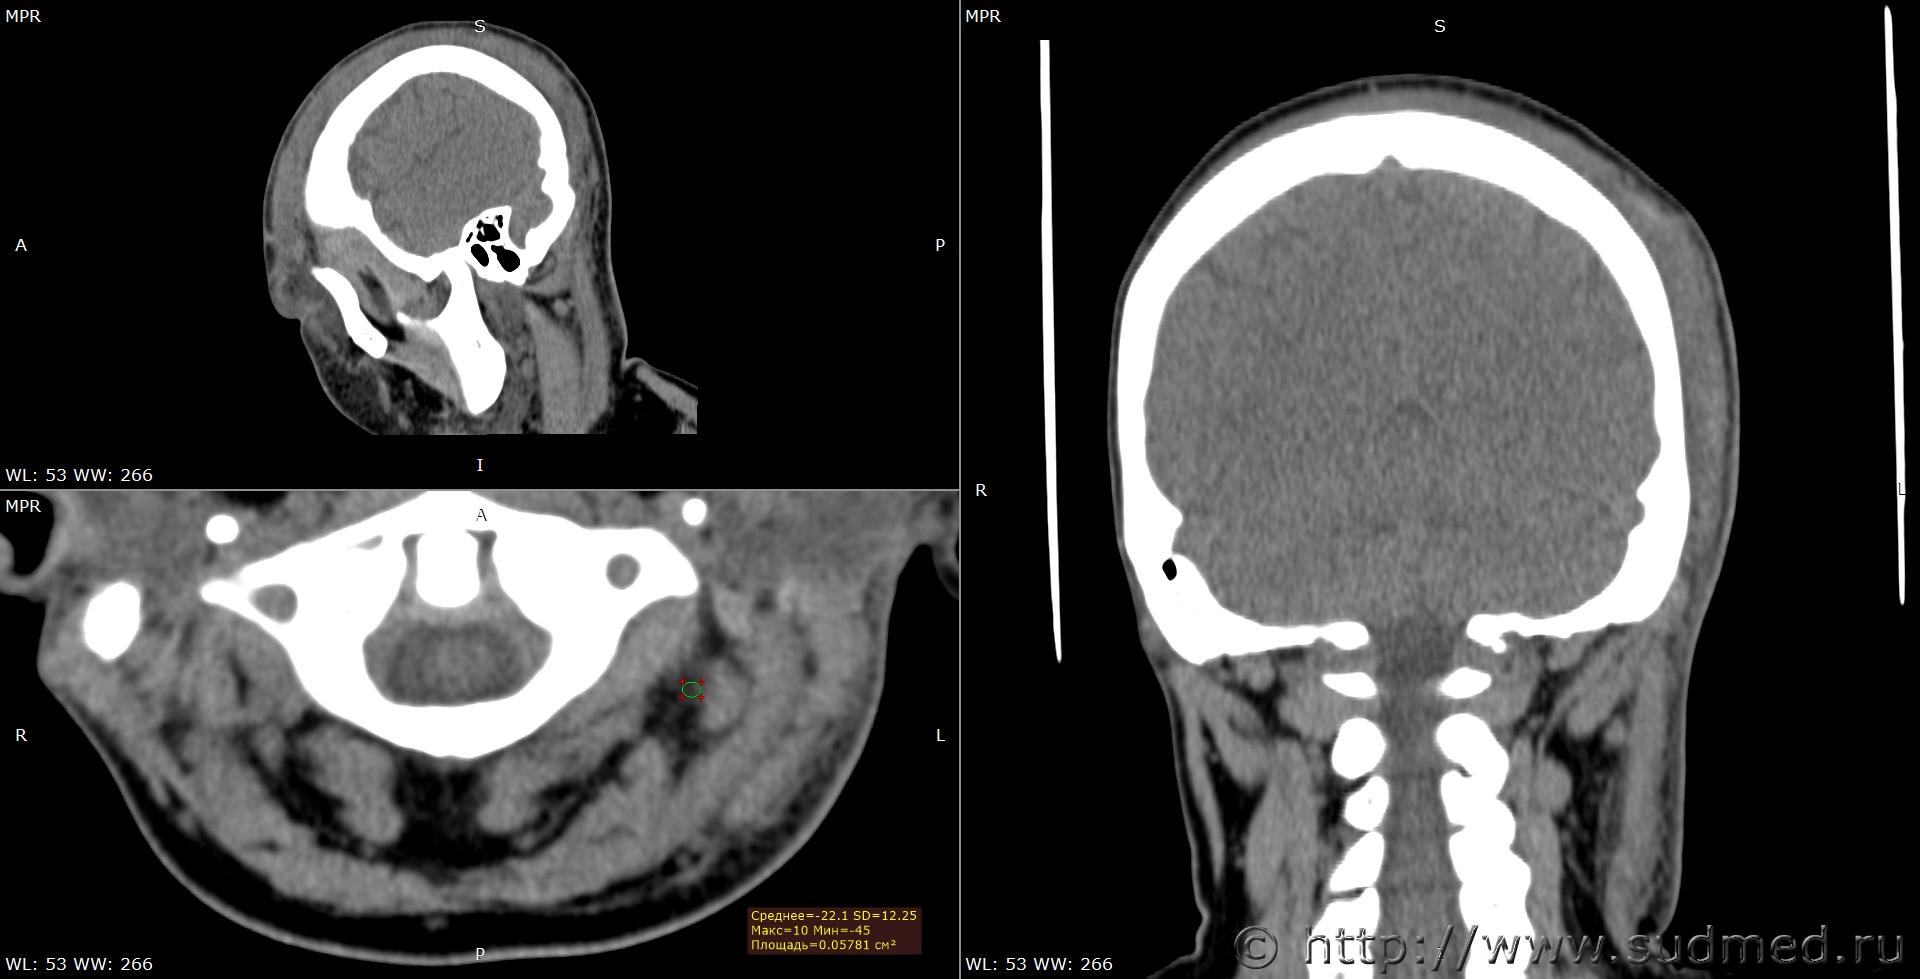

При экспертизе живого лица по медицинским документам встретились переломы шиловидных отростков височных костей. Женщина 39 лет, обратилась за медицинской помощью на 5-е сутки после травмы, тогда же провели РКТ. До этого никуда не обращалась. В протоколе РКТ отметили перелом шиловидного отростка левой височной кости, на снимках перелом на границе верхней и средней трети, дистальный отломок слегка смещен кпереди, каких-либо признаков заживления нет. Длина отростка 2,19 см. Судебная медицина - Прикрепленное изображение Также на КТ визуализируется перелом шиловидного отростка правой височной кости в нижней трети с выраженным смещением, думаю, отрывного характера (его длина 2,01 см), также без каких-либо признаков заживления Судебная медицина - Прикрепленное изображение; и гематома теменной области слева с переходом, в частности, на левую височную область, область левого сосцевидного отростка, левые околоушно-жевательную и скуловую области, левую боковую поверхность шеи Судебная медицина - Прикрепленное изображение, увеличение в объеме, нечеткость контура и разволокнение левой грудино-ключично-сосцевидной мышцы и левой ременной мышцы головы в верхней трети Судебная медицина - Прикрепленное изображение, вокруг них, в том числе кнутри от ременной мышцы, повышение плотности ПЖК Судебная медицина - Прикрепленное изображение; такие же изменения плюс повышение плотности левой подкожной мышцы шеи Судебная медицина - Прикрепленное изображение, увеличение в объеме и нечеткость контура левой околоушной слюнной железы, левая жевательная мышца не изменена Судебная медицина - Прикрепленное изображение. У подъязычной кости вижу нарушения целостности левого большого рога, но окостенение не завершено, края четко не визуализируются, поэтому о характере нарушений целостности не могу судить. Судебная медицина - Прикрепленное изображение Судебная медицина - Прикрепленное изображение В осмотрах врачей какие-либо изменения в области шеи, изменения голоса, соответствующие жалобы не отмечены; на 6-е сутки выставили острый фарингит. Помимо этой травмы есть переломы костей носа, там ничего особенного.